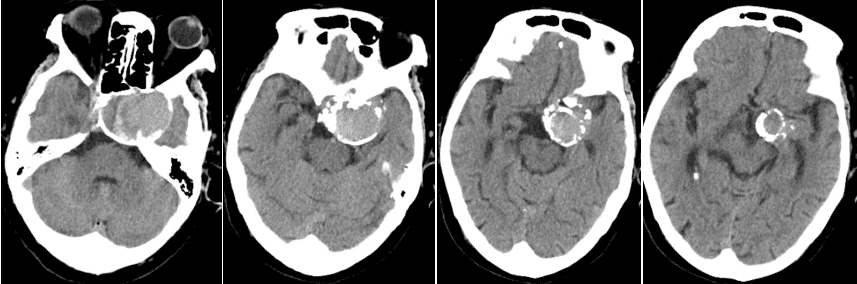

蝶鞍左旁水平见团状高密度影,周围见环形高密度影。

左侧颈内动脉C3段管壁见非钙化斑块,管腔完全闭塞;C5段管壁见钙化斑块,管腔轻度狭窄(0%~29%);C4段动脉瘤,周围见环状钙化,偏右侧见新月形充盈缺损,病灶长径约4.7cm。